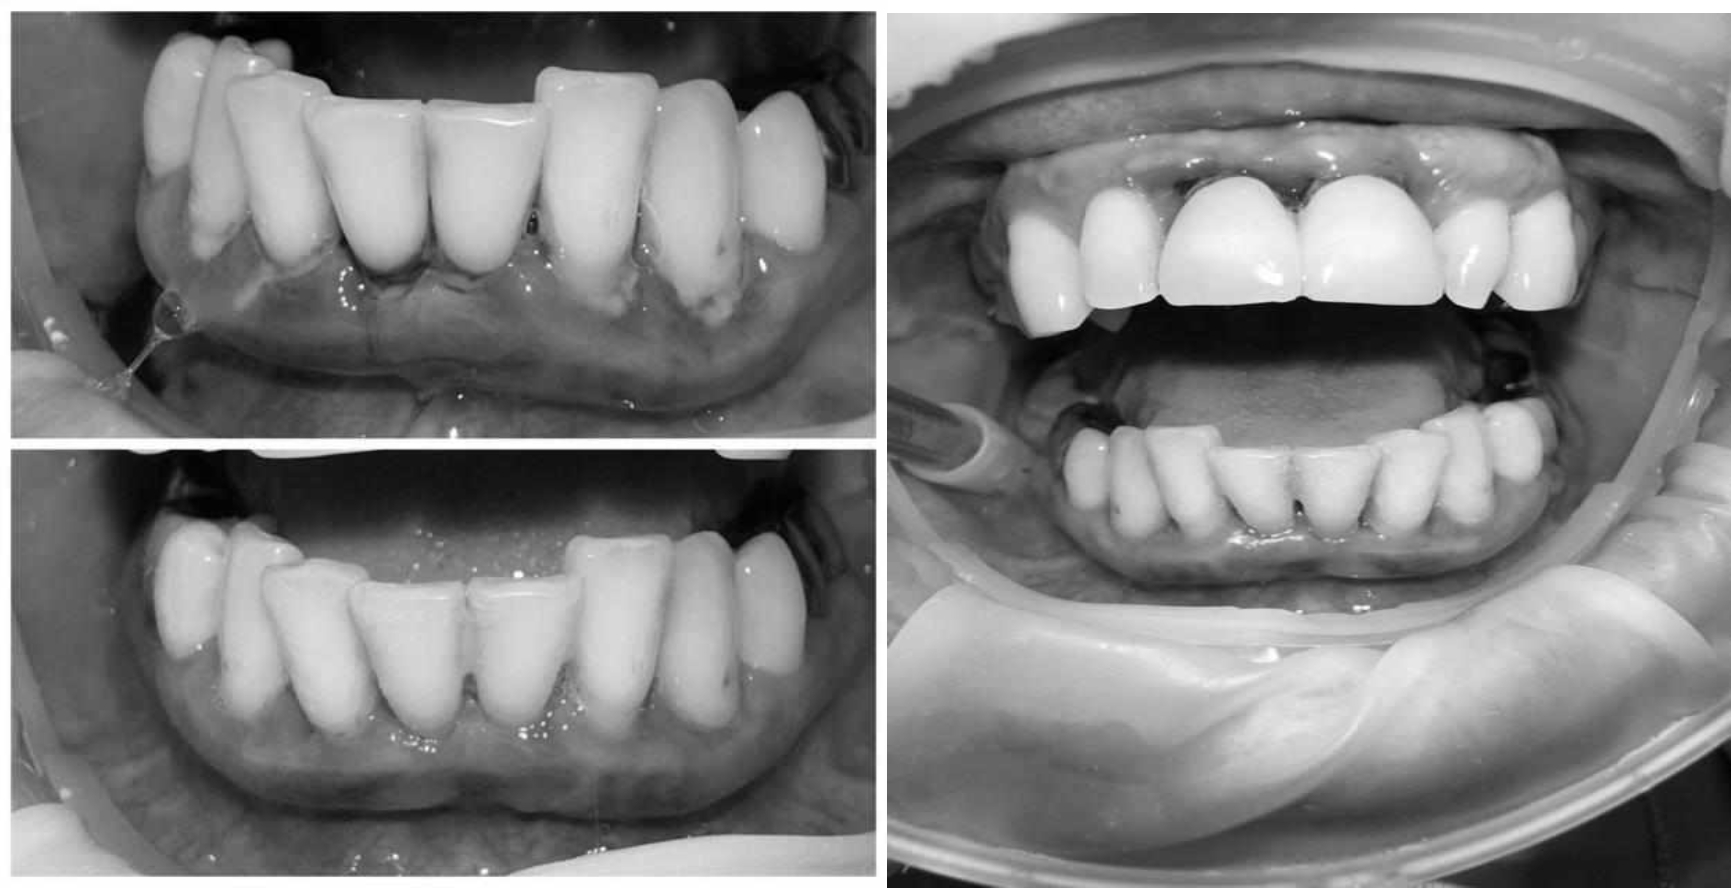

За пародонтологическим лечением обратилась женщина 61 года с жалобами на неприятный запах из полости рта, кровоточивость десен при чистке зубов, подвижность зубов, несостоятельность ортопедических конструкций.

Ранее у пародонтолога не наблюдалась. При осмотре выявлены: неудовлетворительная индивидуальная гигиена полости рта, пародонтальные карманы до 7 мм, обильная кровоточивость и гноетечение из пародонтальных карманов, подвижность зубов 4.2, 4.1, 3.1, 3.2 II степени, обильные над- и поддесневые зубные отложения (рис. 1). На ортопантомограме отмечается резорбция костной ткани до ½ длины корня, очаги остеопороза (рис. 2). Пациенту был поставлен диагноз хронический генерализованный пародонтит тяжелой степени тяжести. При осмотре была составлена пародонтограмма с использованием компьютерного зондирования (рис. 3).

Рис. 2. Ортопантомограмма исходной ситуации пациента состояния полости рта

Для стабилизации пародонтологического статуса было проведено комплексное лечение, которое включало в себя: системную антибиотикотерапию, пациент был обучен гигиене полости рта, были подобраны средства индивидуальной гигиены, была проведена профессиональная гигиена полости рта с использованием ультразвукового скейлера, аппарата Air-flow, проведена поддесневая инструментальная обработка.

В качестве поддерживающего пародонтологического лечения проводилась обработка поверхности корней с применением аппарата «Вектор», диодного лазера. Для домашнего использования были подобраны ополаскиватели с содержанием хлоргексидина, рекомендованы аппликации противовоспалительных стоматологических гелей. После снятия воспалительных явлений пародонта провели шинирование 4.3, 4.2, 4.1, 3.1, 3.2, 3.3 зубов с применением стекловолоконной ленты. Контроль лечения проводился через 1, 3 и 6 месяцев.

Через 6 месяцев при осмотре выявлен удовлетворительный уровень индивидуальной гигиены, отсутствие участков кровоточивости и гноетечения (рис. 4), пародонтальные карманы уменьшились в размерах (рис. 5). Пациент отмечает значительные улучшения. После стабилизации пародонтологического статуса пациент направлен для дальнейшего ортопедического лечения.